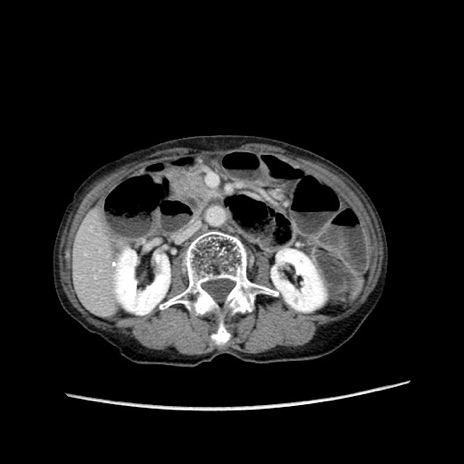

冠状断像

【症例】80歳代女性

【主訴】胸のつかえ感

【現病歴】約9時間前に食後から胸のつかえた感じあり、嘔吐あり、来院。

【既往歴】胃癌(全摘)、胆摘、虫垂炎

【身体所見】心窩部に圧痛あり、反跳痛なし。

【データ】WBC 5700、CRP 0.05